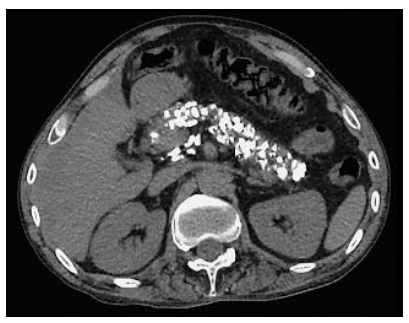

Homem, 45 anos, etilista por 10 anos. Na investigação de uma dor abdominal, realizou a TC abaixo.

Qual sintoma NÃO é esperado nessa situação?

Hipoglicemia